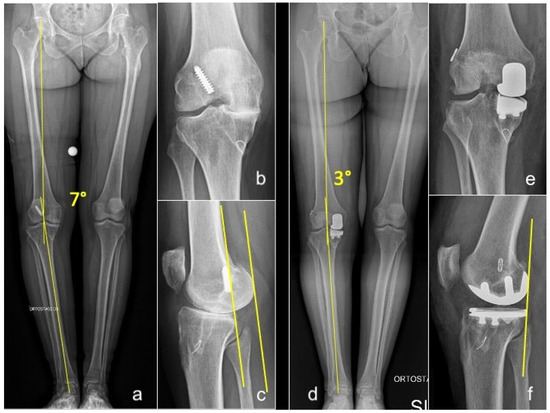

Figure 2. Long-standing whole-leg (a), anteroposterior (b), and lateral (c) radiographs of a 54-year-old female who presented with grade 4 medial OA and failure of a previous ACLR. Postoperative long-standing whole-leg (d), anteroposterior (e), and lateral (f) views after simultaneous medial UKA + revision of ACLR. Yellow lines in (a,d): hip-knee-ankle angle (HKA). Yellow lines in figure (c,f): posterior translation of the femoral condyles consequent to ACL deficiency, corrected after UKA+ACLR.

In open ACLR, UKA was performed first to correct the coronal deformity before placing the ACL graft. After trial reduction in the UKA, the femoral tunnel was created via the arthrotomy, and a guiding wire was passed through it. Then the UKA was cemented and, subsequently, the tibial tunnel was created to prevent cement invasion. The graft was then passed using the guiding wire and secured to the femur and tibia (Figure 2).

The following clinical scores were assessed during follow-up visits: the Knee Society Score (KSS) [24], both clinical and functional (KSS-C and KSS-F); the Tegner Activity Scale (TAS) [25]; and the University of California, Los Angeles (UCLA) Activity Score [26]. Laxity with anteroposterior (AP) translation was assessed clinically using the Lachman test at 30° knee flexion and compared to the contralateral knee. Routine weight-bearing anterior–posterior long-leg radiographs, Rosenberg view [27], true lateral view, and 30° patellar axial view radiographs were obtained preoperatively and at every follow-up visit. The hip–knee–ankle (HKA) angle was measured both pre- and postoperatively, defined by an angle formed by a line connecting the center of the femoral head to the center of the knee, and a second line from the center of the knee to the center of the talus. Varus alignment was defined as a mechanical axis less than 180°. Radiographs were assessed by two trained observers blinded to postoperative outcomes using a Picture Archiving and Communication System (Philips Medical Systems; Sectra-Imtec AB, Linköping, Sweden). All clinical and radiological assessments were independently conducted by two examiners (S.P. and F.B.) who were not involved in the surgical procedures.